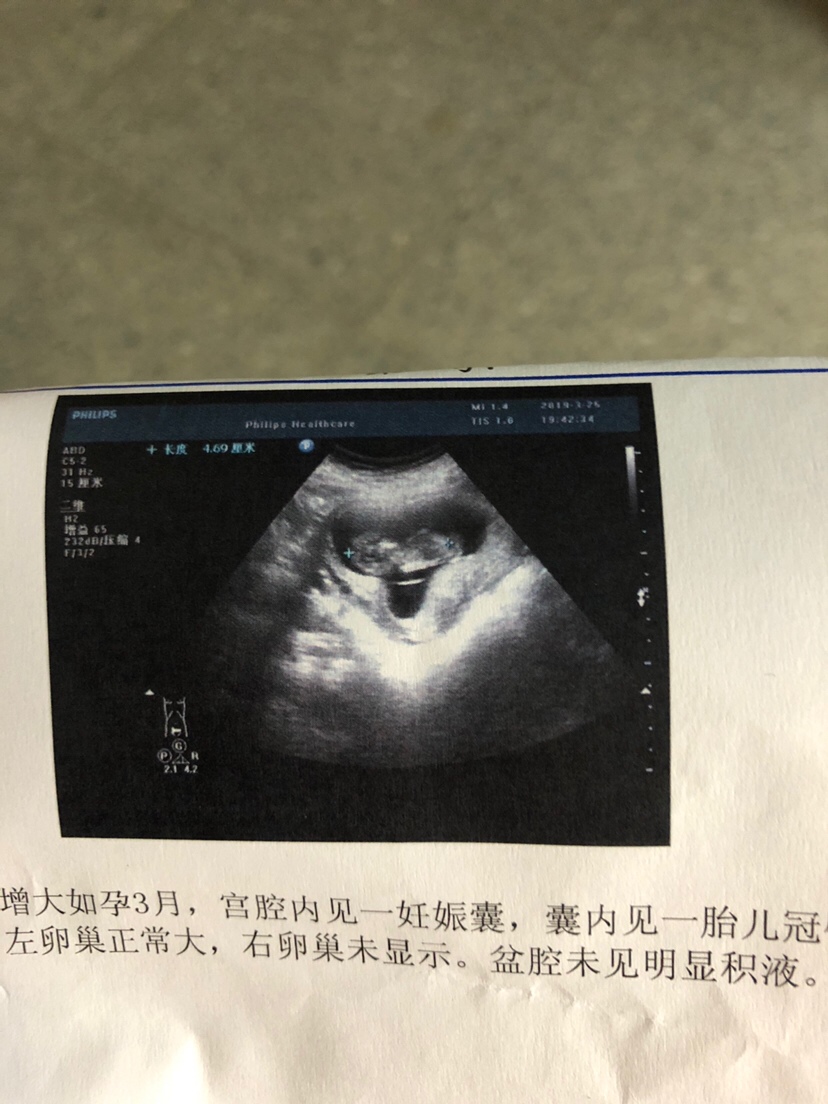

怀孕 孕12周+5天